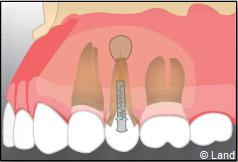

On pratique un acte de chirurgie endodontique lorsque les approches conventionnelles sont techniquement difficiles ou impraticables. L’objectif est de retirer une partie de la racine qui ne peut être désinfectée par les techniques classiques et est la cause d’une infection et parfois de l’abcès qui en découle.

Une anesthésie et une incision semi lunaire sont réalisées et le lambeau de gencive est récliné.

Il faut localiser le bout de la racine de la dent atteinte, procéder au décollement de la lésion avec une curette à bords tranchants, couper et enlever la partie de racine infectée.